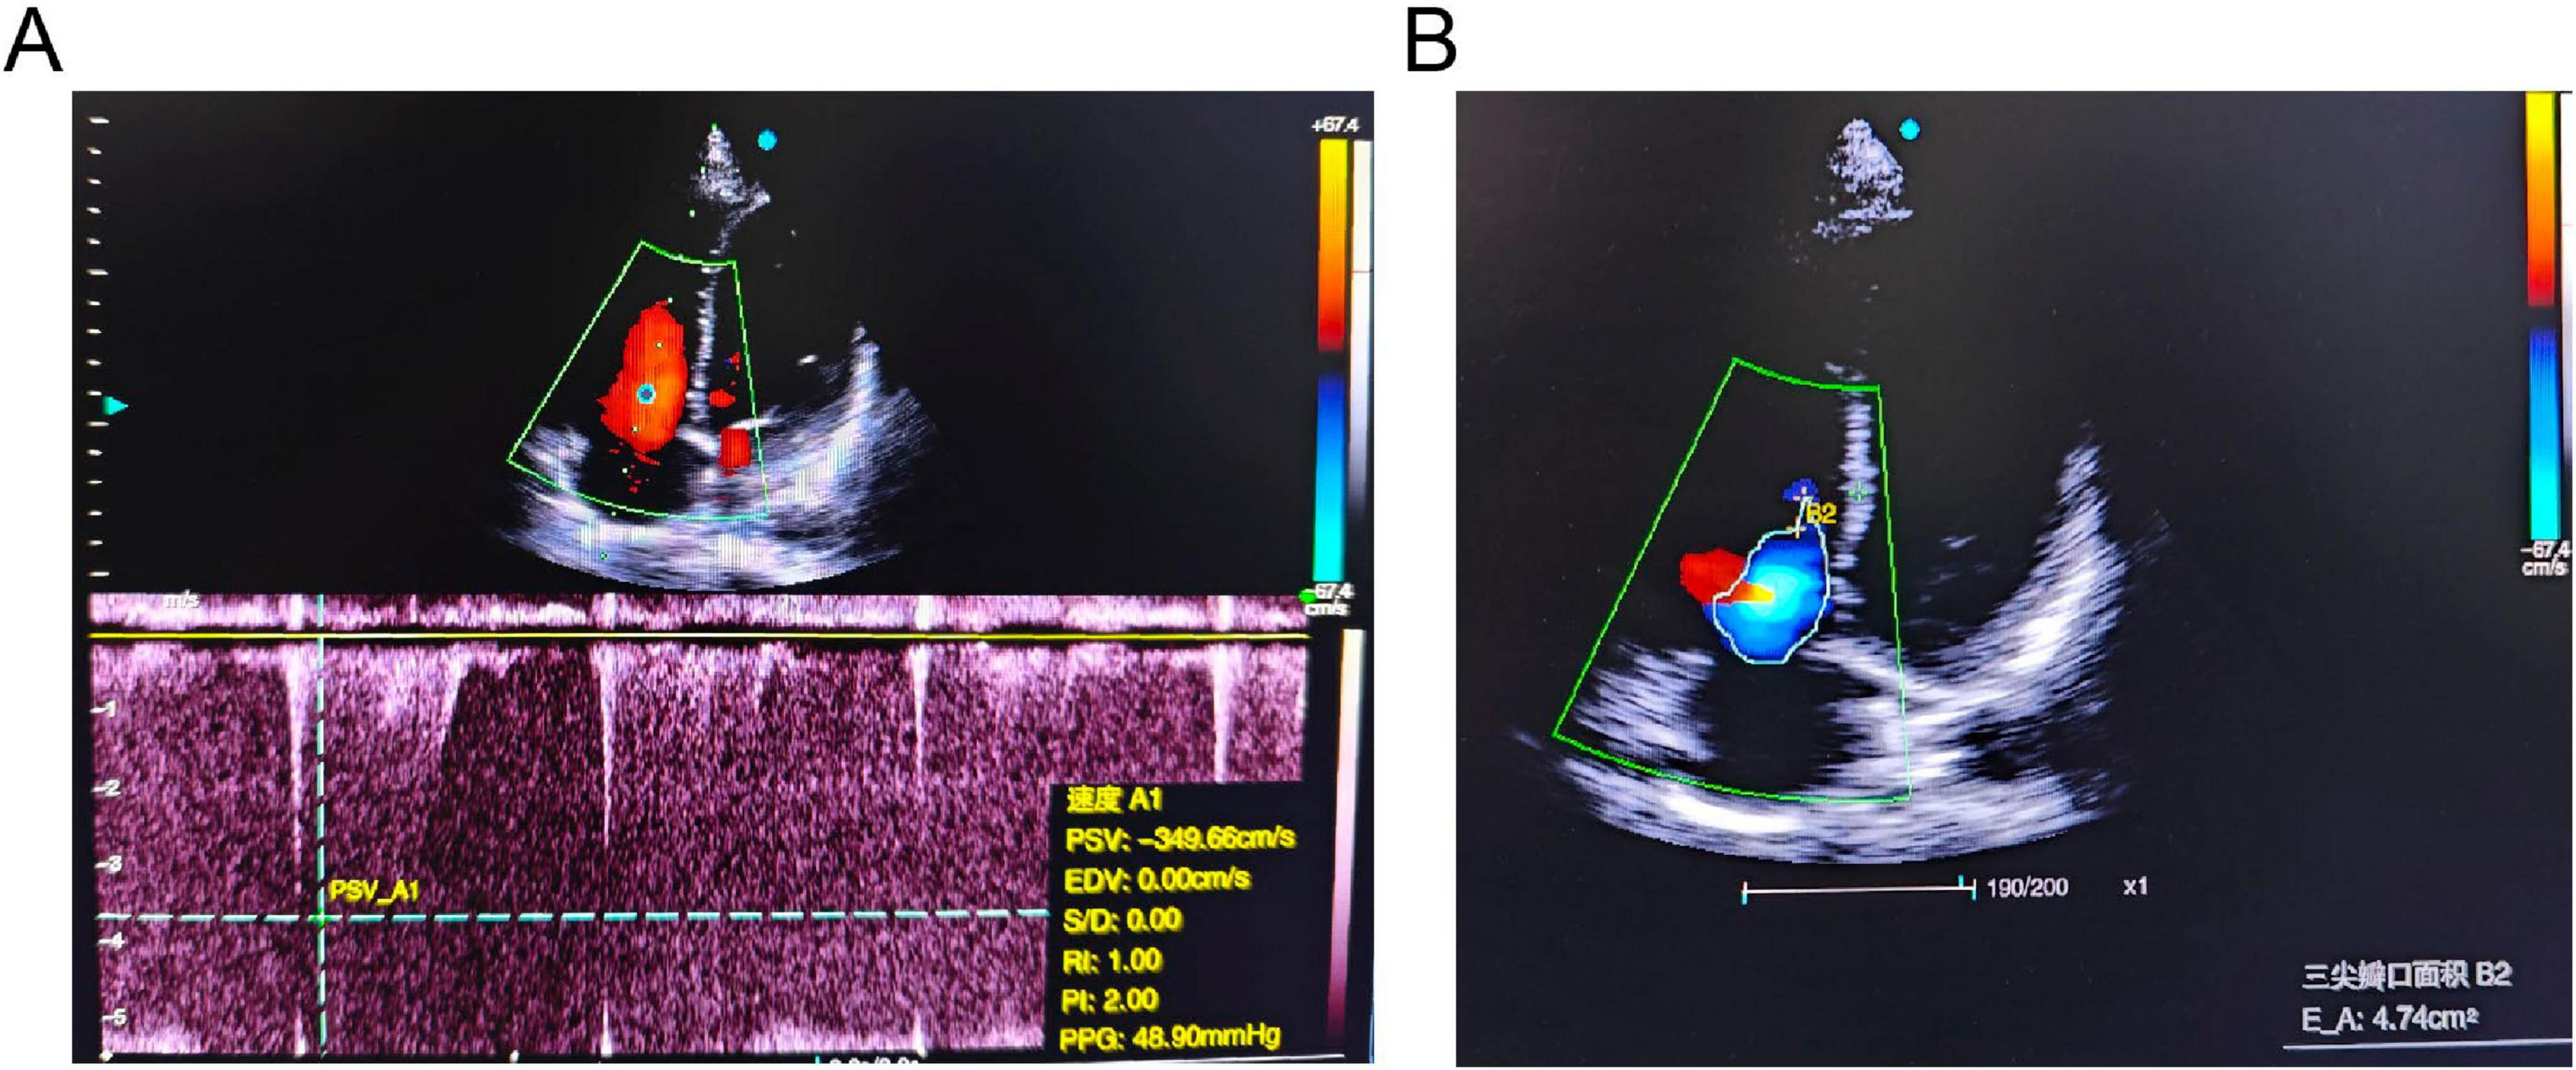

Background: The high-altitude environment characterized by hypobaric hypoxia can cause significant damage to the cardiovascular system, particularly vascular endothelial function, and is a significant trigger for acute and chronic mountain sickness. High-altitude pulmonary hypertension (HAPH) is a serious complication induced by prolonged exposure to high altitude, characterized by abnormally elevated pulmonary artery pressure and increased right heart load, which can progress to right heart failure and be life-threatening. This article aims to enhance clinicians' understanding of this disease through two cases of HAPH in young males. Case Description: Case 1 was a 21-year-old male who developed progressively worsening chest pain, shortness of breath, and amaurosis fugax after living at an altitude of 4800 meters for 4 months. Case 2 was a 20-year-old male who experienced exertional dyspnea accompanied by amaurosis fugax and a brief loss of consciousness after 18 months of residence at 4300 meters. Both patients were previously healthy with normal cardiopulmonary function before moving to high altitude. Physical examination upon presentation revealed significant hypoxemia (oxygen saturation 80% and 82% on room air, respectively). Echocardiography in both cases clearly demonstrated right atrial and right ventricular enlargement, moderate tricuspid regurgitation, with estimated systolic pulmonary artery pressures (sPAP) as high as 55 mmHg and 56 mmHg, respectively. Chest CT confirmed right heart enlargement and main pulmonary artery dilation. After systematic evaluation excluded other etiologies, HAPH was diagnosed. Discussion: The core pathophysiology of HAPH is hypoxia-induced pulmonary vasoconstriction and remodeling. These cases demonstrate that even for young, healthy individuals, prolonged exposure to extremely high altitudes can lead to severe pulmonary hypertension and right ventricular dysfunction. Diagnosis requires a combination of high-altitude exposure history, clinical symptoms, evidence of hypoxemia, and echocardiographic findings. The most fundamental treatment for diagnosed HAPH patients is removal from the high-altitude hypoxic environment, making early recognition and intervention crucial. Conclusion: The high-altitude environment poses a serious threat to the cardiovascular systems of susceptible individuals. For patients with a history of high-altitude residence who present with relevant symptoms, clinicians should maintain a high index of suspicion for HAPH and conduct timely screening and diagnosis to prevent adverse outcomes.